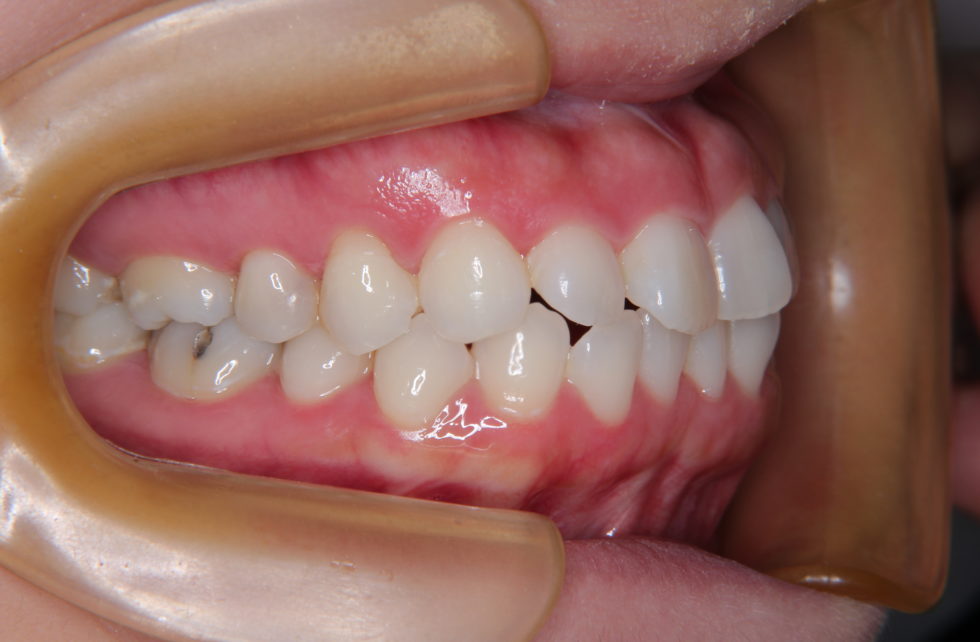

初診時32歳女性。口元の突出を伴う上下顎前突のケース。

上下顎前歯が前方に突出していたため、口元の突出と口唇閉鎖不全を招いていました。上下顎左右側第一小臼歯(4番目)を抜歯して頂き、上顎は舌側(裏側)マルチブラケット装置を使用し、上下顎前歯の後退を行いました。前歯の後退を行なったことにより口元の突出も改善し、口唇閉鎖も無理なく行えるようになりました。   動的治療期間は2年2ヶ月間